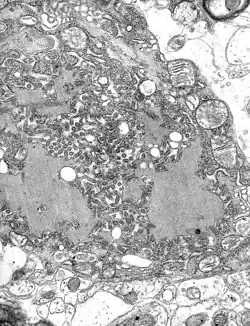

| MRI scan image shows high signal in the temporal lobes and right inferior frontal gyrus in someone with herpes simplex encephalitis. | |